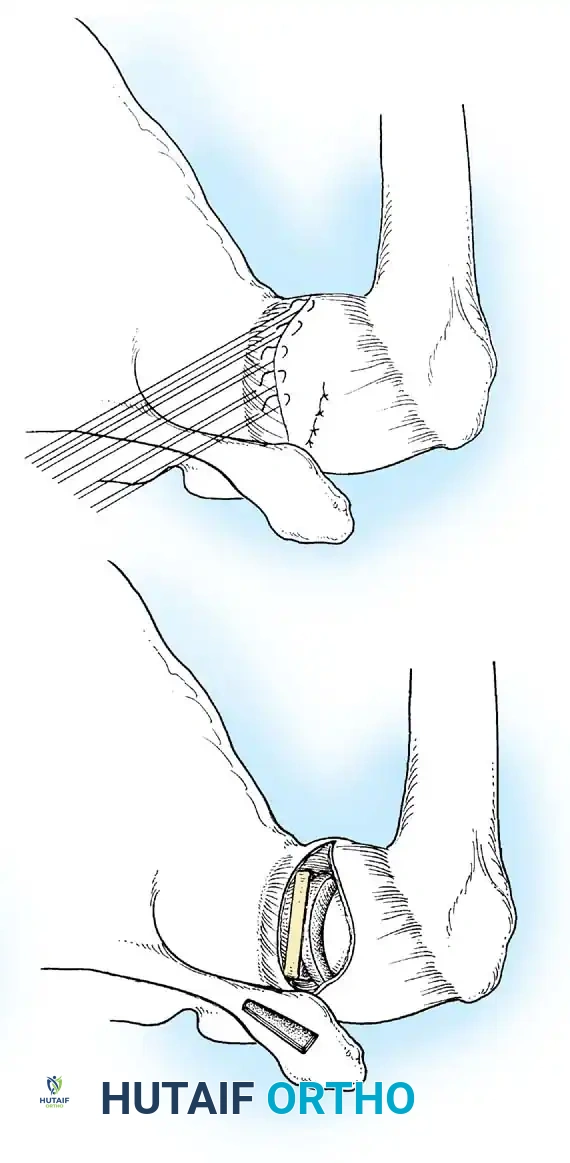

Baker et al. arthroscopically evaluated acute dislocations, finding that 38% involved intrasubstance ligamentous failures, while 62% were avulsions from the glenoid. Bigliani et al. biomechanically tested the IGHL complex, revealing that failure occurs at the glenoid insertion (40%), midsubstance (35%), or the humeral insertion (25%). Humeral avulsion of the glenohumeral ligament (HAGL lesion), noted by Wolf et al. in 9% of acute dislocations, is a critical pathology that must not be missed, as standard Bankart repairs will fail to address it.

Bipolar Bone Loss

SURGICAL WARNING: Failure to recognize and address significant bipolar bone loss is the leading cause of recurrent instability following soft-tissue stabilization.

A Hill-Sachs lesion is an impaction fracture of the posterolateral humeral head, created when the head is driven against the hard anterior glenoid rim during dislocation. Burkhart and DeBeer introduced the concept of the "engaging" Hill-Sachs lesion, which levers the humeral head out of the joint when the arm is abducted and externally rotated.

Concurrently, anterior glenoid rim fractures or attritional bone loss can occur. Itoi demonstrated that a 20% loss of the anterior glenoid width critically compromises stability, rendering soft-tissue repairs (like an isolated Bankart repair) biomechanically insufficient. Advanced imaging (3D CT or MRI arthrography) is mandatory to quantify bone loss.

- HAGL lesions that are technically challenging to repair arthroscopically.